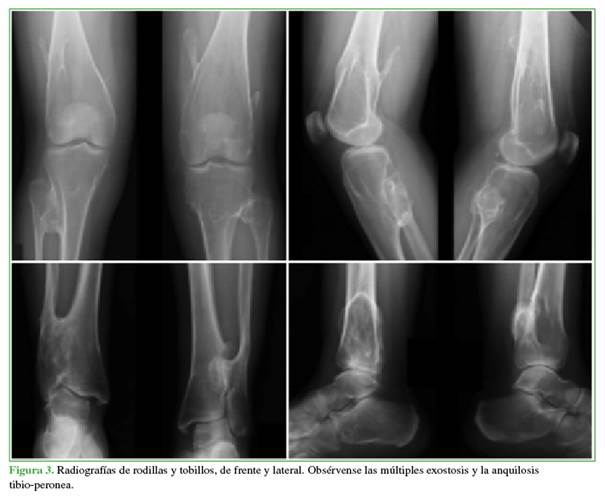

Mujer de 42 años de edad, con antecedentes familiares de EMH en su línea paterna que consultó, por primera vez, por coxalgia izquierda de dos años de evolución. Refería un dolor intenso con la carga de peso y limitación de las actividades cotidianas. La movilidad de la cadera era de 120º de flexión, 30º de abducción y limitación de las rotaciones. El puntaje de cadera de Harris9 era de 75. En la radiografía de pelvis, se observó una displasia bilateral de cadera con subluxación de la cabeza femoral y protuberancias óseas (exostosis) en ambos trocánteres menores hacia la cabeza femoral (Figura 1). La cadera izquierda tenía un ángulo cervico-diafisario de 165º, incongruencia acetabular y signos artrósicos que eran más evidentes en la tomografía computarizada (Figura 2). En las radiografías de rodillas y tobillos, se visualizaban las múltiples exostosis y una anquilosis tibio-peronea (Figura 3).